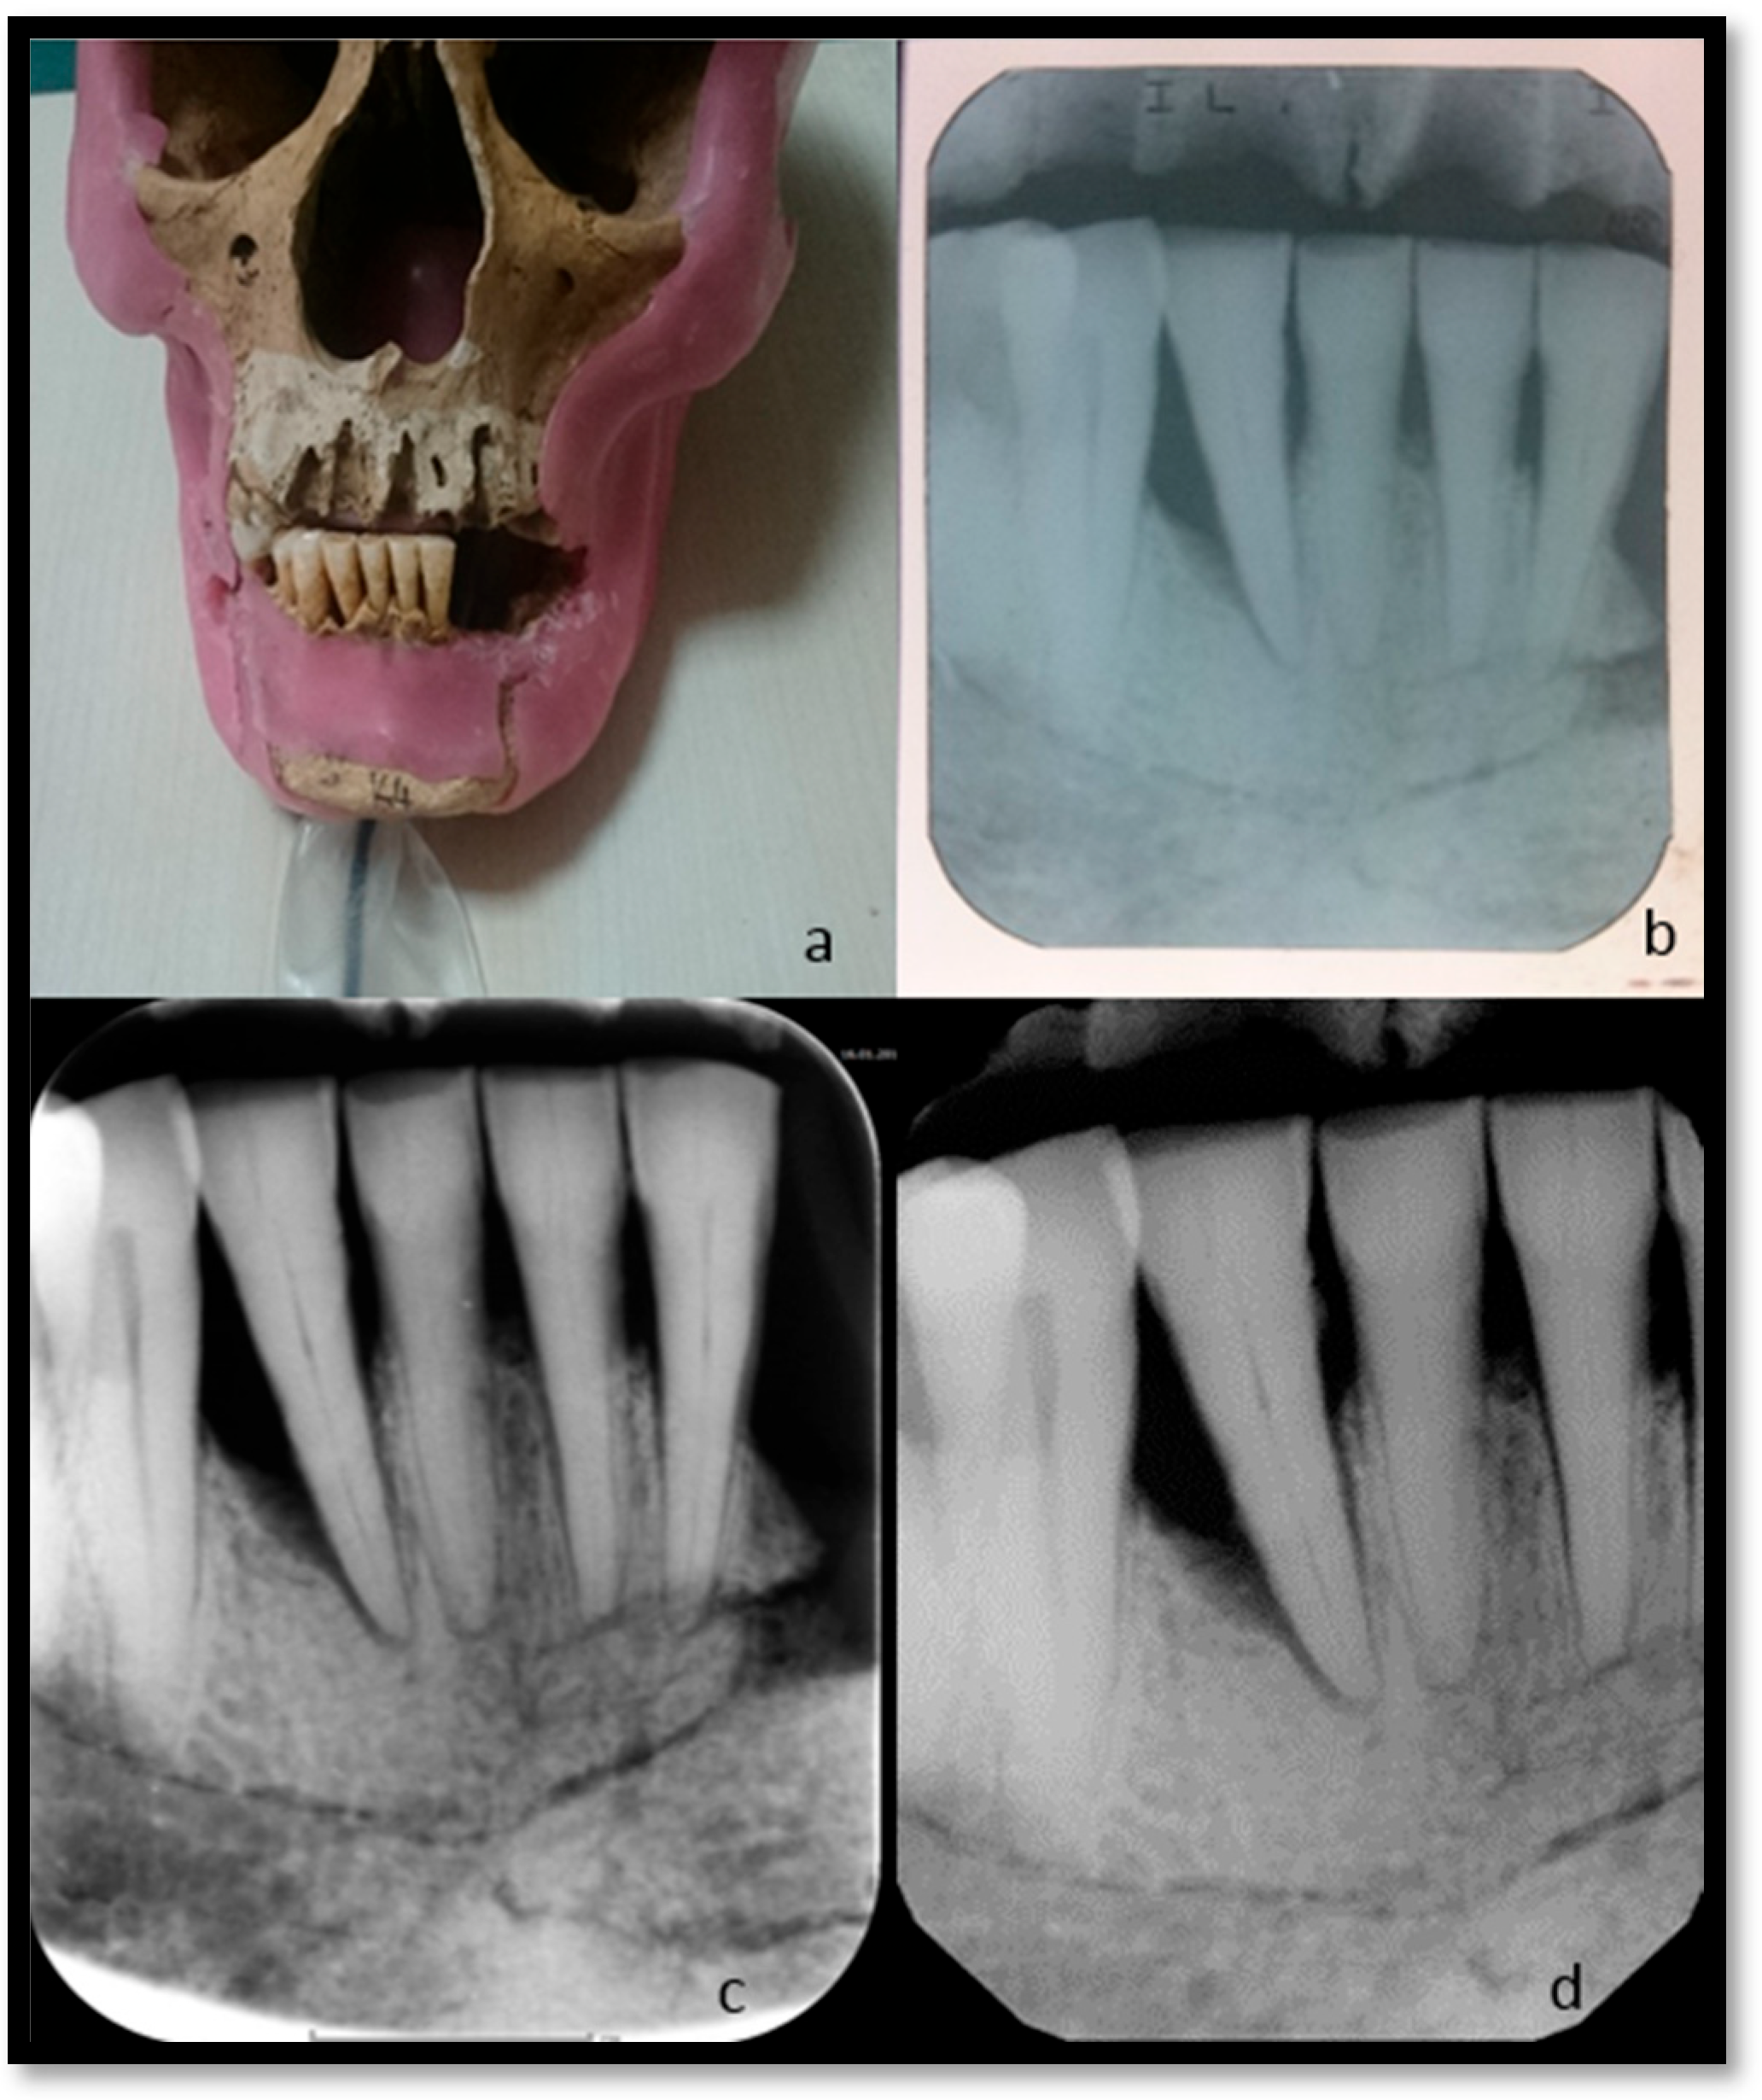

With each device, images were obtained by irradiating at the recommended times in conventional (C), photo-stimulable phosphor plate (P), and RVG (R) systems. Image quality was not evaluated in our study. It was determined how the image would look when irradiated at the times recommended by the manufacturers (Figure 3).

Figure 3. (a) Dry skull. (b) Conventional X-ray film. (c) Phosphor plate image. (d) RVG image.